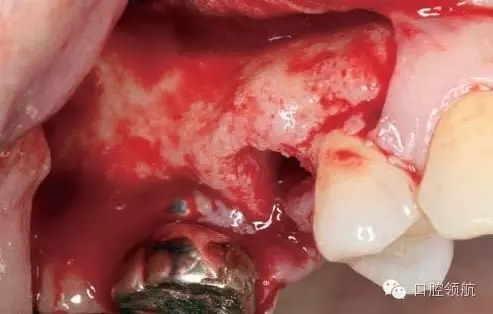

術(shù)前口內(nèi)未見種植體周圍有炎癥等異常表現(xiàn)(圖2),翻開黏骨膜瓣后,10年前手術(shù)入路的痕跡在頰側(cè)骨面已經(jīng)觀察不到了(圖3)。

圖2 ( 左上第五顆牙)拔除后即刻的口內(nèi)像。

圖3 黏膜剝離后的口內(nèi)像。10年前手術(shù)入路的痕跡在頰側(cè)骨面已經(jīng)看不到。